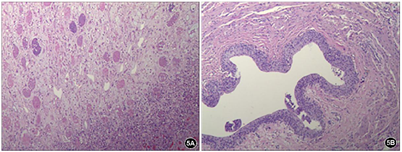

入院后予万古霉素、美罗培南抗感染及支持对症治疗,仍有发热,体温波动于38℃左右,于住院第5天偶诉胸痛、胸闷,可耐受,可自行缓解,复查心脏超声:肺动脉分叉处与降主动脉间见一囊实性回声包块,显示范围约74.8 mm×55.9 mm,内为等回声及无回声。于住院第6天胸痛、胸闷症状加重,伴多汗,每次持续1~20 min不等,前倾位稍缓解,伴呼吸、心率增快,发作时监测血压明显增高,收缩压最高达170 mmHg,含服硝苯地平后可暂时缓解。查体:精神反应欠佳,面色稍苍白,呼吸频率33次/分,三凹征阴性,双肺呼吸音粗,左肺呼吸音减低,可闻及少许痰鸣音,心率101次/分,心音有力,律齐,腋前线第4肋间可闻及2/6级收缩期杂音,足背动脉搏动弱,余未见明显阳性体征。行纵隔增强CT(图2):降主动脉起始段明显缩窄,直径约2.3 mm,狭窄段远端约17 mm处可见降主动脉前缘一膨大造影剂影突出腔外,最大截面约4 5mm×31 mm,上下长度约32 mm,主动脉裂口处宽度约19.4 mm,突出部分周围可见环状软组织密度影包绕,考虑假性动脉瘤形成;复查血常规:WBC 16.17×109/L,Hb 92 g/L,HCT 28.20%,Plt 357×109/L,N 87.0%,L 8.2%,CRP 69.11 mg/L。完善术前检查,于住院第9天全麻低温体外循环下行降主动脉瘤切除、主动脉缩窄切除、人工血管置换术、肺脓肿引流术。术中探查见主动脉峡部缩窄,内径0.3 cm,长约1.2 cm,缩窄段以远2.0 cm处起始主动脉破口,长约3.0 cm,横径1.5 cm,瘤体深入至左肺叶内,5.0 cm×6.0 cm×6.0 cm大小,左肺整体不张实变,张力较高。术中诊断:主动脉缩窄、降主动脉假性动脉瘤、感染性心内膜炎、肺炎并肺脓肿。病理检查示:壁内纤维组织增生及片状出血伴炎症反应,符合假性动脉瘤。术后呼吸机辅助通气,继续予美罗培南+万古霉素抗感染、硝普钠控制血压,体温正常,病情逐渐恢复。于住院第18天,患儿偶诉腹痛,可自行缓解,伴有低热,37.4℃,当天夜间,患儿突然腹痛加重,伴面色苍白、烦躁、意识淡漠。体格检查:T 37.4℃,P 120次/min,R 40次/min,BP右上肢110/65 mmHg。意识模糊,面色及口唇苍白,颈软,无抵抗,呼吸稍促,三凹征阴性,双肺呼吸音粗,未闻及明显湿啰音,心率120次/min,心音有力,律齐。腹韧,右下腹压痛、反跳痛及肌紧张,肝脾肋下未触及,肠鸣音正常,四肢末梢凉,CRT 4 s。急查腹部超声示:右腹部异常回声包块(血肿形成?),急诊腹部增强CT(图3):右肾动脉近段纤细,远端未见显示,右肾实质内可见数条纤细较淡造影剂血管影走行,右肾静脉未见明确显示。右肾受压右移,其内侧及下缘周围可见大片状不均质密度影,大小约90 mm×88 mm×121 mm,内部密度不均,未见明显强化,考虑为巨大血肿。立即全麻下行多学科联合手术(心内科、心外科、普外科、泌尿外科),行腹主动脉造影+肾动脉球囊扩张术+单侧肾切除术+腹膜后血肿清除术。行腹主动脉造影示右肾动脉造影剂外溢。右腹部脐上2 cm长约18 cm横切口,依次打开皮下、腹直肌、腹膜,见腹腔大量凝血块、不凝积血,右下腹膜外巨大血肿,肝脏受压,肠道移向右腹部,右肾呈暗红色,已失活,肾动脉不规则破裂达2/3直径。球囊充液扩张阻断腹主动脉近右肾动脉开口处血流(图4)。清除腹腔及腹膜外凝血块、积血等,暴露肾蒂,游离右肾动静脉、输尿管,7#丝线分别双重结扎、切断右肾动静脉,回抽球囊开放血流,未见出血。同时结扎、切断右侧输尿管,取出失活右肾(图4),充分止血,盐水2000 ml冲洗腹腔。术中诊断:肾动脉破裂;腹膜后血肿。病理诊断:右侧肾脏广泛出血、坏死(图5)。术后体温不稳定,血压仍高,且转氨酶逐渐升高,于住院第33天将万古霉素更换为利奈唑胺(斯沃),后体温逐渐正常,于住院第63天将抗生素降级为舒普深,3 d后停抗生素,观察2 d无症状,临床治愈,于2018年6月29日出院。

根据药敏试验积极抗感染治疗,心外科全麻低温体外循环下行降主动脉瘤切除、主动脉缩窄切除、人工血管置换术、肺脓肿引流术。术后9 d出现腹痛,腹部超声及CT提示巨大血肿,心内科行腹主动脉造影明确部位后给予球囊充液扩张阻断腹主动脉近肾动脉开口处血流,普外科及泌尿外科联合立即行腹膜后血肿清除术及单侧肾切除术,术后继续抗感染及降压治疗。